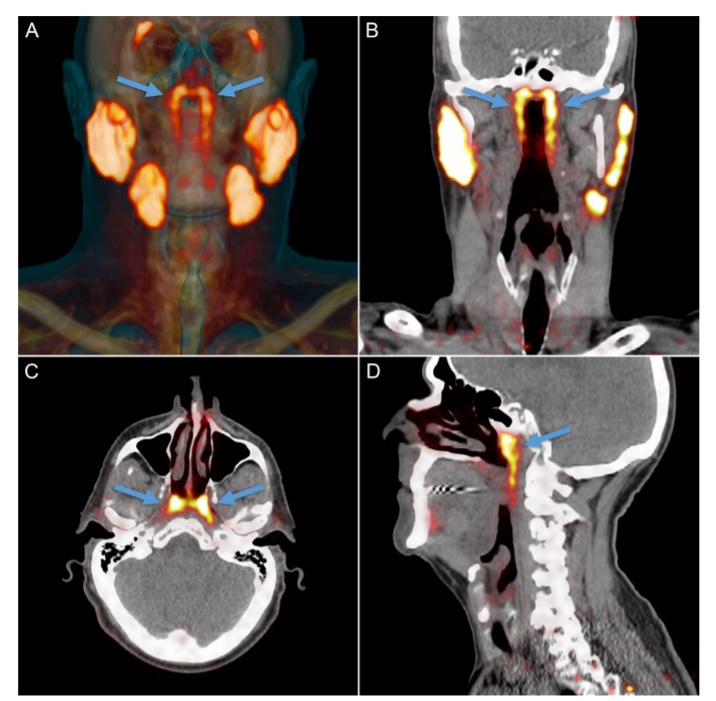

除了以上五种公认的进化理论外,最近,荷兰癌症研究所(NKI)的放射肿瘤学家Wouter Vogel意外发现了一组秘密的新器官:藏在人体喉咙深处上部的唾液腺,隆凸唾液腺。这个发现可能会对癌症的治疗产生重要影响。

在以往的医学记载中,人类只有三个明显的唾液腺——舌下腺、颌下腺和腮腺,分别位于舌头下方、下颌下方和脸颊后部的下颌背面。除此之外,咽喉和口腔粘膜组织中或许也散布着上千个极小的唾液腺。它们分泌唾液,帮助我们咀嚼、吞咽和消化食物,并保持我们的口腔湿润及牙齿健康。而这次新发现的隆凸唾液腺位于鼻子后面一块被称为咽鼓管隆凸的软骨上,平均长度约1.5英寸(即3.9厘米)。

Wouter Vogel是在探查头部、颈部或脑部癌症放疗后的唾液腺损伤(导致消化、语言和口腔感染增加等问题)时,发现这组从未被描述和记录过的颈部唾液腺的。为了证实人体的隆凸唾液腺这一最新发现的非偶然性。Vogel及其同事对100名患者进行了扫描(由于研究者是聚焦前列腺癌,所以其中99位患者为男性),还解剖了两具尸体,最终发现所有人都拥有这一“新的”腺体。这一惊喜发现于2021年10月16日正式发布在《放射治疗与肿瘤学》(Radiotherapy & Oncology)上。

新器官的发现,可以帮助医生在使用放射性治疗法治疗癌症的时候,设法避免在患者的头部和脖子部位,对唾液腺进行照射。因为在使用放射性疗法对头部、颈部进行治疗时,我们可以避免照射到这些唾液腺而导致这些唾液腺受到影响。